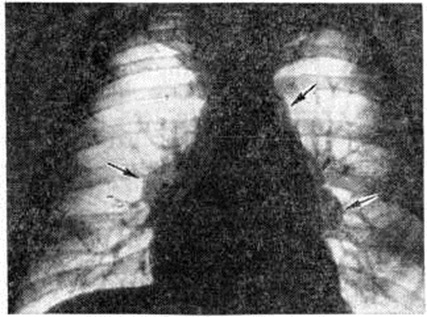

Рис. 6.

Рентгенограмма грудной клетки в прямой проекции при I стадии саркоидоза внутригрудных лимфатических узлов: корни лёгких и тень средостения расширены, с полициклическими очертаниями за счёт увеличенных лимфатических узлов (указаны стрелками), тень сердца имеет митральную конфигурацию.

Информация об Ordo Deus Перейти в оглавление сайта

Рис. 7.

Рентгенограммы грудной клетки в прямой (а) и боковой (б) проекциях при II стадии саркоидоза лёгких и внутригрудных лимфатических узлов: корни лёгких и тень средостения расширены, в средних и нижних отделах лёгких видны тени густо расположенных однотипных очагов и сетчато-тяжистое изменение лёгочного рисунка.

Рис. 8.

Рентгенограмма грудной клетки в прямой проекции при III стадии саркоидоза легких: корни лёгких тяжистые, видны индуративные и сетчато-тяжистые фиброзные изменения в прикорневых отделах лёгких.

При I стадии Саркоидоз органов дыхания рентгенологически определяется расширение корней лёгких и средостения за счёт опухолевидного увеличения всех групп лимфатических, узлов грудной полости, преимущественно лимфатических узлов корней лёгких. Очертания корней лёгких и средостения имеют полициклический характер, тени передних и задних групп лимфатических, узлов средостения, накладываясь друг на друга, создают симптом «кулис», увеличение лимфатических, узлов средостения из-за суммации теней придаёт сердцу митральную конфигурацию (рисунок 6). На томограммах выявляется, что увеличенные лимфатических, узлы располагаются по окружности крупных бронхов в области их деления на долевые, сегментарные и субсегментарные ветви. Иногда лимфатических, узлы образуют дугообразные вдавления стенок бронхов, в ряде случаев ведут к нарушениям бронхиальной проходимости — образуются участки гиповентиляции, ателектаза.

Для II стадии характерна картина очаговой диссеминации: определяется избыточный, петлистый рисунок в прикорневых и нижних отделах лёгких (стадия IIа), образование мелких (милиарных) очагов (стадия IIб), появление более крупных очагов диаметром 3 — 5 миллиметров (стадия IIв), формирование крупных очагов диаметром более 6 миллиметров (стадия IIг). Наиболее постоянным является сочетание интерстициальных изменений с очаговыми, занимающими преимущественно прикорневые отделы средних и нижних лёгочных полей (рисунок 7).

III стадия характеризуется наличием распространённого фиброза, участков цирроза лёгких (рисунок 8).